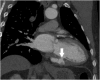

"Cases of SCMR" is a case series on the SCMR website (https://www.scmr.org) for the purpose of education. The cases reflect the clinical presentation, and the use of cardiovascular magnetic resonance (CMR) in the diagnosis and management of cardiovascular disease. The 2022 digital collection of cases are presented in this manuscript.

Keywords: Arrhythmogenic cardiomyopathy; COVID-19; Cardio-oncology; Congenital Heart disease; Coronary artery aneurysm; Hydatid disease; Hypertrophic cardiomyopathy; Metastatic disease; Myocardial. infarction; Myocarditis; Takotsubo; Vaccine associated myocarditis; Viability.